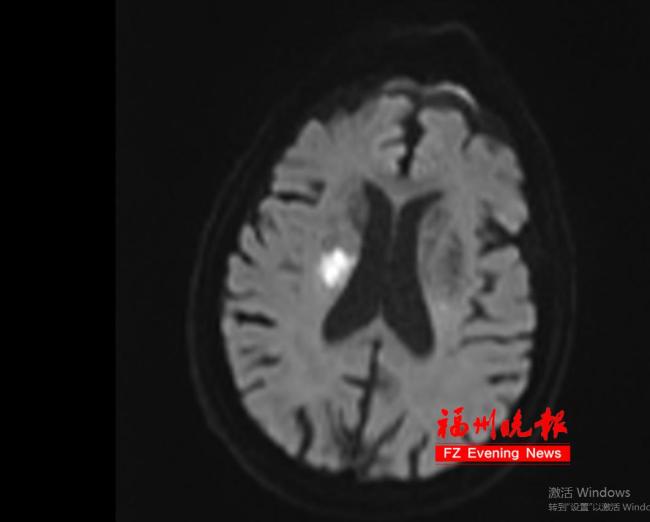

流感初期,张大叔出现发热、咳嗽、浑身酸痛乏力等症状。他平日没有基础疾病,以为是小感冒,打算“扛一扛”,不去医院。没想到,3天后张大叔突然右侧肢体无力,口角开始歪斜,说话含糊不清。家人发现情况不对,立刻拨打120,将他紧急送往附近的福建省级机关医院。入院后,医生迅速开启“卒中绿色通道”。通过头颅CT检查,医生确诊张大叔患上了急性脑梗死。幸好送医及时,医生立即实施了静脉溶栓治疗。经过治疗,张大叔的右侧肢体逐渐恢复了力气,说话也清楚了不少。一周后,他基本康复了。

张大叔为何会突然脑梗呢?福建省级机关医院神经内科吴美娜副主任医师指出,这和他近期感染流感密切相关。流感病毒入侵人体后,不仅会在呼吸道作乱,还可能对血管系统发起攻击。有研究数据显示,流感确诊后的15天内,脑梗死的发病风险是平时的2.88倍,即便对45岁以下的人群,流感也被视作脑梗死的诱发因素之一。